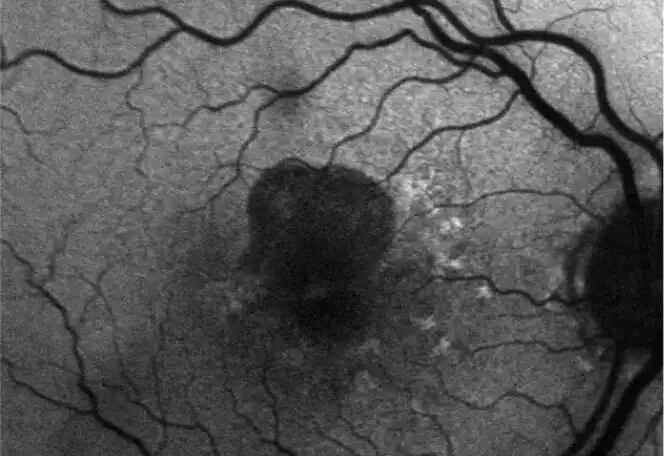

INDICATION

IZERVAY™ (avacincaptad pegol intravitreal solution) is indicated for the treatment of geographic atrophy (GA) secondary to age-related macular degeneration (AMD)

Neovascular AMD

- In clinical trials, use of IZERVAY was associated with increased rates of neovascular (wet) AMD or choroidal neovascularization (7% when administered monthly and 4% in the sham group) by Month 12. Over 24 months, the rate of neovascular (wet) AMD or choroidal neovascularization in the GATHER2 trial was 12% in the IZERVAY group and 9% in the sham group. Patients receiving IZERVAY should be monitored for signs of neovascular AMD.